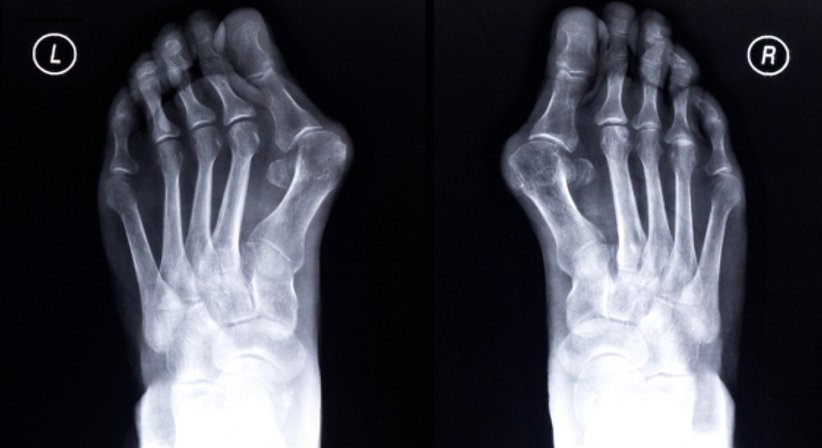

Im weiten Feld der orthopädischen Krankheiten gibt es allerdings immer wieder Situationen, in welchen eine operative Therapie nicht zu vermeiden ist. Im Bereich vom Fuß ist das beispielsweise der Hallux valgus (Deformität der Großzehe), bei welchem sich die Beschwerden mit konservativen Maßnahmen (Physiotherapie zur Kräftigung vom Fuß, Schuheinlagen mit Abstützung des Fußgewölbes und des Mittelfußknochens etc.) zwar bessern lassen, die Korrektur der Fehlstellung ist allerdings nur durch eine Operation möglich.

• Hallux valgus